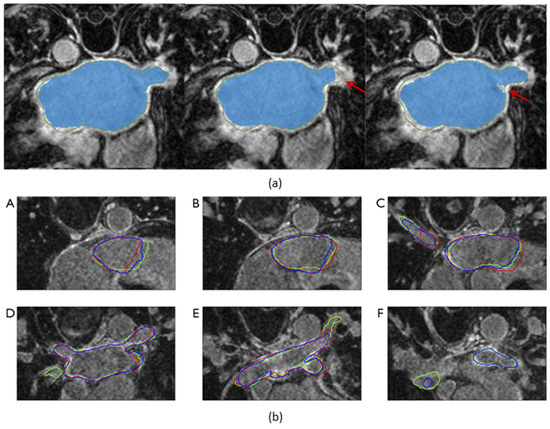

Figure 5.

Visualization of the output segmentation maps superimposed on axial slices of late gadolinium-enhanced magnetic resonance imaging scans. (a) Comparison of the output segmentation maps. The green contours and the blue masks represent the ground truth and the model’s output segmentation maps, respectively. From left to right: the model with both the symmetric multilevel supervision (SML) structure and the uncertainty-guided loss function, the model with only the SML structure, and the model with only an auxiliary supervision branch added to the decoder. Red arrows point out disagreements between the model output and the ground truth. (b) This shows a decline in segmentation accuracy in the vicinity of the pulmonary veins. (A–F): axial slices 15%, 25%, 40%, 60%, 75%, and 85% along the longitudinal axis of the left atrium. The green, red, and blue contours represent the segmentation maps of the ground truth, 2-dimensional segmentation model, and 3-dimensional segmentation model, respectively. The 2-dimensional segmentation model completely failed on the slice 85% along the axis. Figure source: (a) [27], (b) [26].

The impact of individual components of a proposed method can be evaluated by systematically removing these components and observing the impact on the model’s performance. Du et al. [25] enhanced its architecture by gradually introducing DPMs, MSCMs, GBMPMs, and a deep supervision mechanism, resulting in an improved DSC with each addition. Liu et al. [27] compared their proposed model with two other segmentation models. The first model had only an auxiliary supervision branch added to the decoder, while the second model had an SML structure but lacked an uncertainty-guided loss function. Their results indicated that incorporating an auxiliary supervision branch to the encoder improved both DSC and HD, while additionally including an uncertainty-guided loss function further improved the segmentation of the fuzzy surface of the LA, as illustrated in Figure 5a, leading to a reduction in HD.

While high performance in LA segmentation has been demonstrated by state-of-the-art segmentation models, suboptimal segmentation performance has been reported by multiple papers [17,25,26] in regions containing substructures of the LA. Specifically, Razeghi et al. [17] and Borra et al. [26] reported local segmentation performance in regions containing the PVs and the MV. Razeghi et al. [17] conducted 2D segmentation of the LA, MV, and PVs separately. While LA segmentation resulted in a DSC of 0.91 ± 0.02, which is consistent with the other state-of-the-art segmentation models, the segmentation of the PVs and the MV resulted in a DSC of 0.61 ± 0.08 and 0.73 ± 0.08, respectively, showing a decline in overall segmentation performance. Similarly, Borra et al. [26] examined the segmentation performance of the LA along its longitudinal axis, which was divided into three sub-volumes: adjacent to the MV, containing the LA body, and encompassing the PVs. While DSC remained relatively stable in the middle sub-volumes containing the LA body, a significant decrease was observed in the sub-volumes adjacent to the MV and encompassing the PVs. In these sub-volumes, 2D segmentation exhibited a greater decrease in performance compared to 3D segmentation, with a notably low DSC observed in the sub-volume containing the PVs, as shown in Figure 5b. Furthermore, Liu et al. [27] demonstrated that using V-net [41] resulted in high segmentation uncertainty in the regions with the PVs, while the addition of the SML structure as well as the uncertainty-guided loss function reduced the segmentation uncertainty. The PVs play a critical role in the onset of AF [12], but their shapes are highly complex and vary significantly between patients. In patients selected to receive catheter ablation, the most frequently practiced technique is PV isolation, which aims to electrically isolate the triggers in the PVs from the LA [8]. For the safety and effectiveness of PV isolation, it is crucial that the PVs can be segmented accurately. Future research should explore more accurate segmentation techniques to address the challenging shape of the PVs.